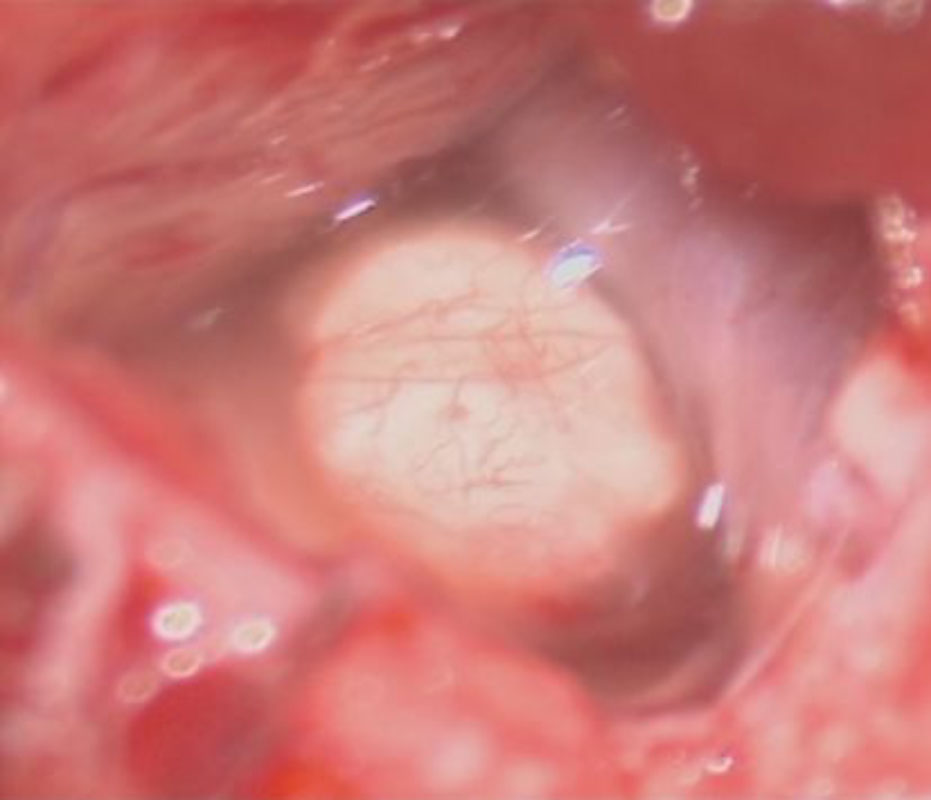

摘出 前

摘出 中